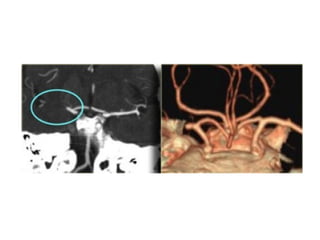

MRA with non-visualization of the left transverse sinus, since the venous anatomy is

variable, this can be due to absence of the transverse sinus or thrombosis, the T1

clearly demonstrates, that there is a transverse sinus on the left, so the MRA

findings are due to thrombosis

The same patient , CT shows the dense thrombosed transverse

sinus (yellow arrow) , the FLAIR shows the venous infarction

in the temporal lobe